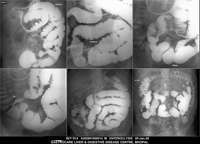

Section: ENTEROCLYSIS

Total: 205 Cases